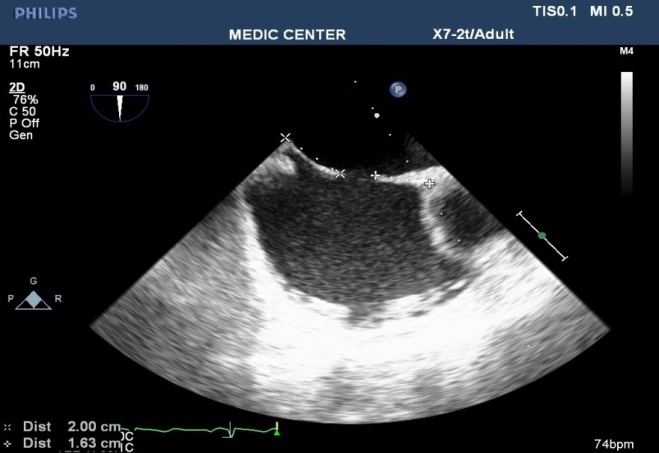

The X-plan mode can be used to estimate the maximal diameter of defect in two orthogonal planes. Three-dimensional (3D) TEE imaging is an important adjunct to 2D imaging because multiplanar reconstruction ensures that the defect is measured accurately.

Three-dimensional (3D) TEE images can be rotated to demonstrate the defect from the RA or LA side in evaluating the secundum atrial septal defect rims. This improves understanding of their shape and relationships to surrounding intracardiac structures.

Multiple ASDs account only 4%, 3D TEE with wide sector can detect and visualize all the shunts through IAS (Figures 22-37).

Figure 22. 2DTEE multiplane at 90⁰ ( Bicaval view ) visualizing a secundum ASD